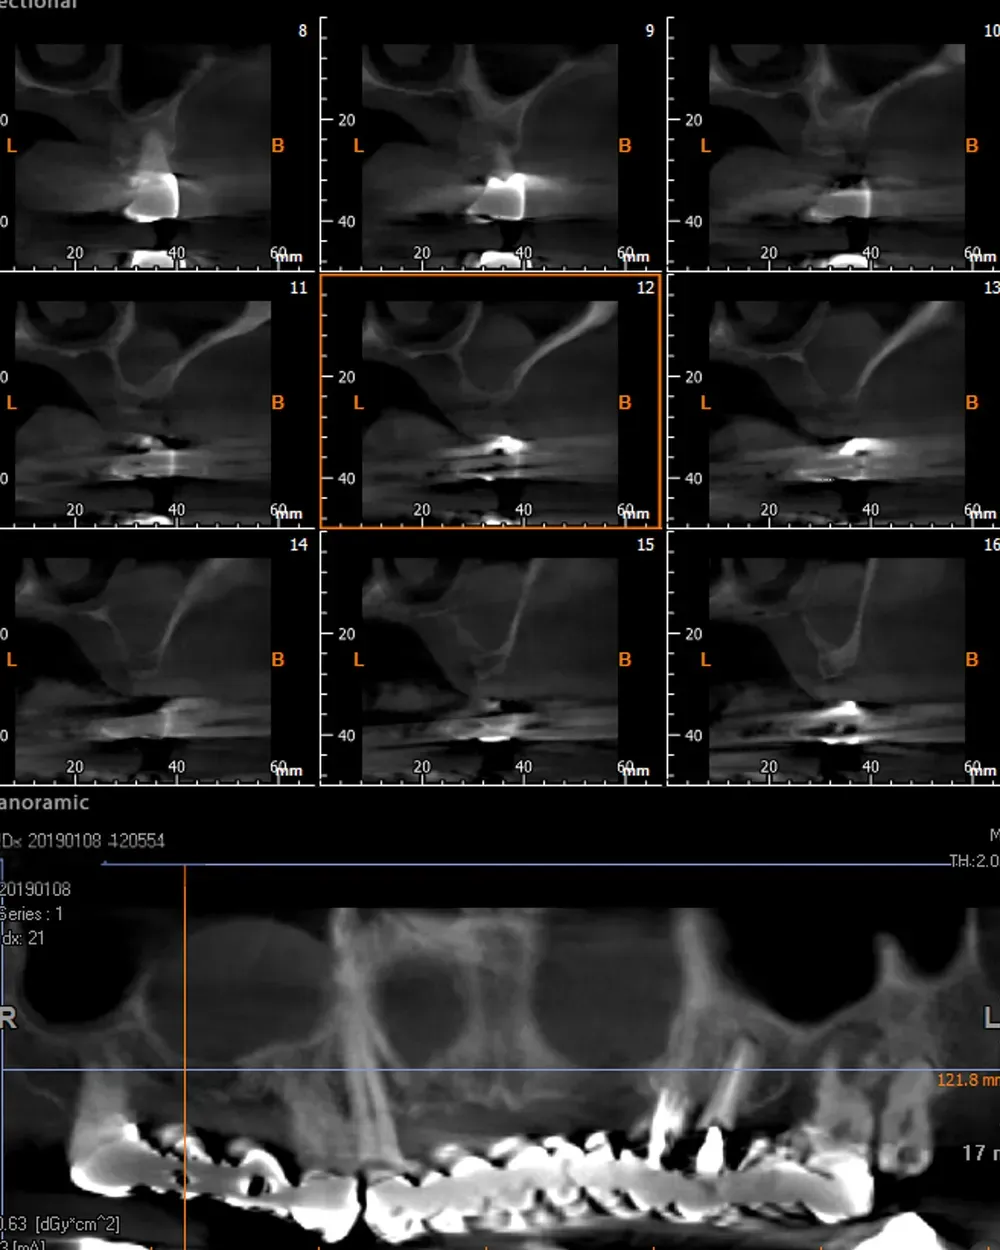

Sul lato sinistro, l’atrofia dopo la rimozione dei denti e la rigenerazione era comunque meno grave e rientrava nell’ambito delle categorie S1-S2 CCARD. La prossima immagine è la CBCT della zona mascellare sinistra prima delle estrazioni.